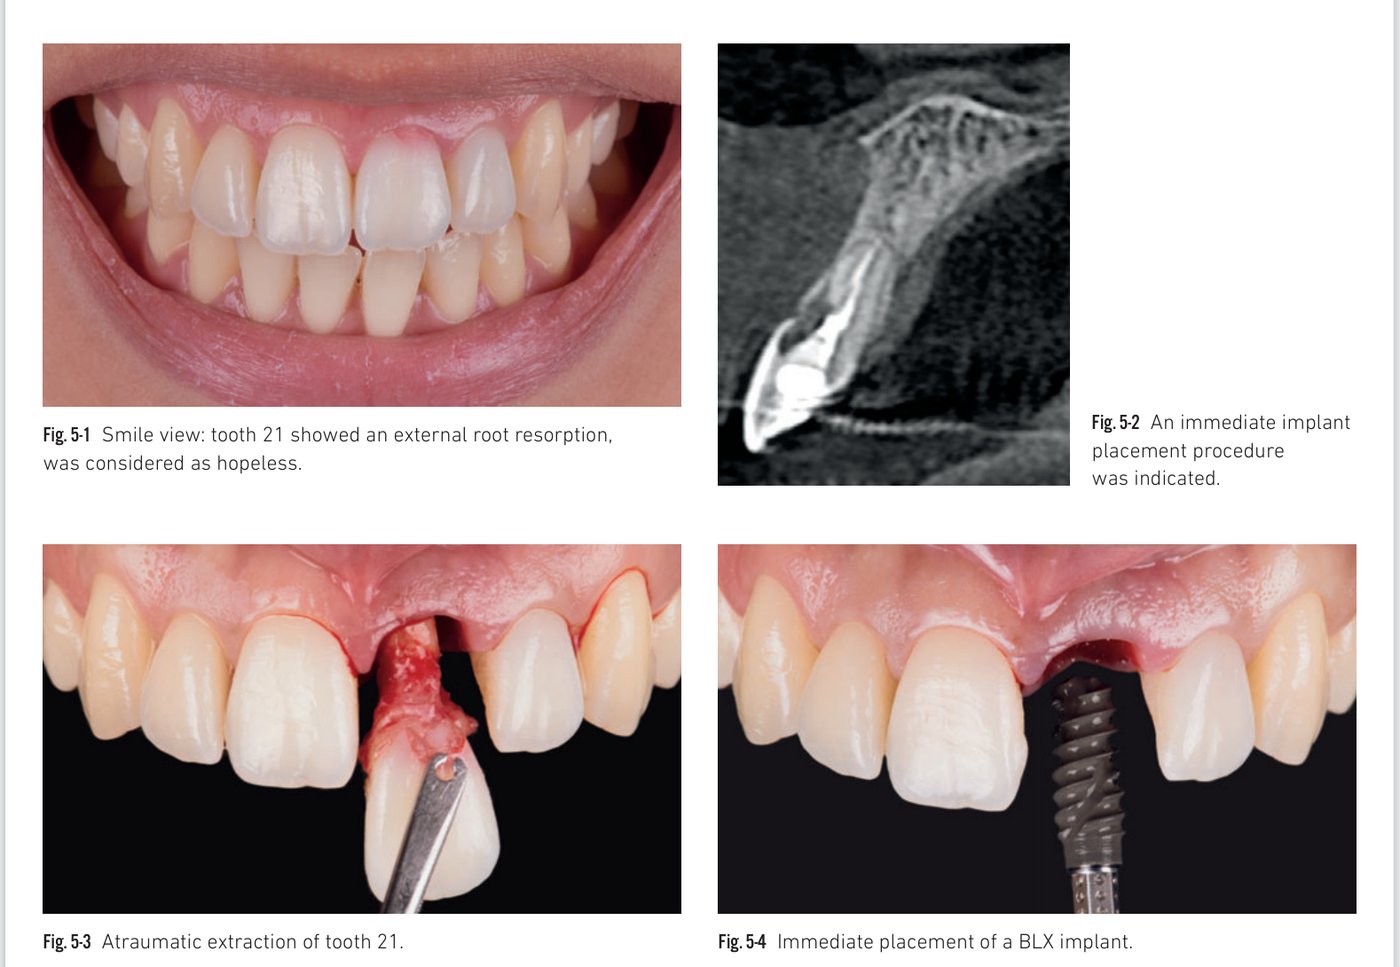

Immediate implant in a central incisor site — chairside temporary crown

The immediate implant-supported temporary crown is of paramount importance for healing and shaping surrounding tissues. In immediate placement cases, placing the implant through a guide with a fully pre-fabricated crown is rarely satisfactory due to palatal cortex constraints. Mastering a simple chairside protocol — bonding a temporary abutment to a digitally designed hollow crown — allows fabrication of a temporary crown in minutes, with an emergence profile that is concave buccally and straight or slightly convex proximally.

Clinical situation 5, page 1: CBCT, extraction, and BLX placement